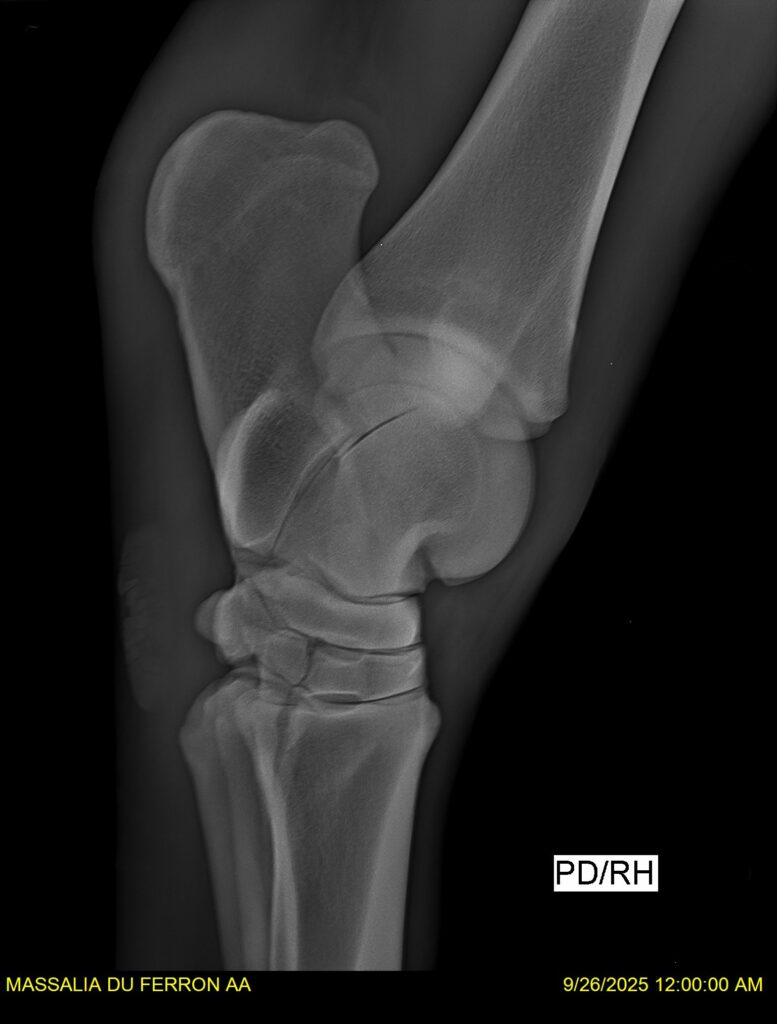

MASSALIA DU FERRON, jument qui prendra 4 ans par PRESTIGE KALONE x TRESOR DU RENOM. Un mental en or et un véritable sens de la barre ! Facile d’accès ! Bonne énergie et bons moyens. Souche moderne et très intéressante. Transport OK, maréchalerie OK, santé RAS, Bilan clichés radios OK.

RADIOS et COMPTE RENDU